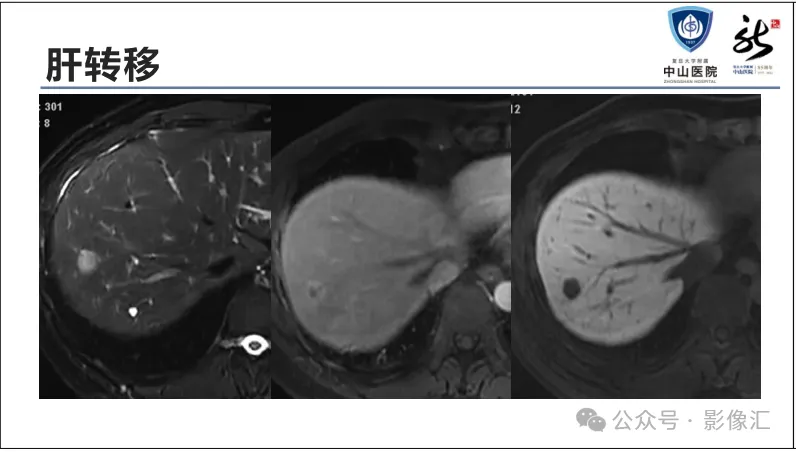

肝胆特异性对比剂增强肝胆图像判读方法与策略,课件来源于网络,作者复旦大学附属中山医院放射科饶圣祥教授。